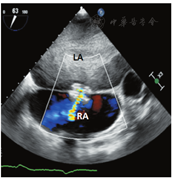

心房分流器置入过程的超声引导与监测:手术开始前,经食管超声多切面观察,排除心腔内血栓、房间隔缺损及房间隔膨胀瘤,同时再次确定适应证。术中经食管超声引导下,房间隔穿刺鞘沿导丝进入右房(图3A),穿刺鞘尖端于卵圆窝后下部进行穿刺(图3B)。穿刺后,预先塑形的加硬钢丝经房间隔穿剌部位至左心房内,其后递送10 mm外周动脉球囊至房间隔处,以8个标准大气压行反复球囊扩张。超声实时监测扩张部位、过程、大小。退出球囊后送入输送系统,选择20-6 mm的D-shant心房分流器,在经食管超声监测下,将其释放于房间隔两侧(图4A,B),经食管超声显示分流器形态、位置正常,分流孔径约6 mm,并清晰显示左向右分流信号(图5),三维超声观察分流器形态及其与周围组织毗邻关系;即刻右心导管测压,左房压由分流器置入前15 mmHg降至置入后8 mmHg(1 mmHg=0.133 kPa),释放分流器。术后送监护病房观察。患者自诉症状明显改善,1 d后从监护室转回普通病房,3 d后出院。3个月后复查心脏超声,分流器形态位置正常,患者自觉生活质量提高。